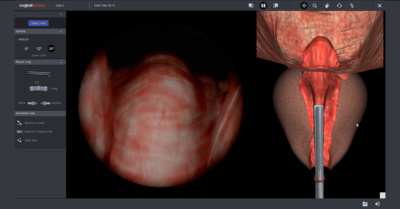

This article, published in Simulation in Healthcare, discusses the critical role of simulation in addressing healthcare challenges worldwide. It outli…